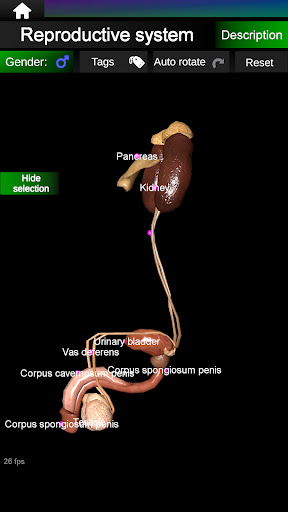

Internal Organs in 3D Anatomy لـ Vodafone Smart N9 Lite

(الأجهزة الداخلية في)

Internal Organs 3D Anatomy 3.4

يمكنك هنا تنزيل ملف حزمة تطبيق أندرويد "Internal Organs 3D Anatomy" الخاصة بجهازVodafone Smart N9 Lite مجانًا، نسخة ملف حزمة تطبيق أندرويد - 3.4 للتحميل على Vodafone Smart N9 Lite اضغط ببساطة على هذا الزر. إنه سهل وآمن. نحن نقدم فقط ملفات حزمة تطبيق أندرويد الأصلية. إذا انتهكت أية مواد موجودة في الموقع حقوقك قم بإبلاغنا من خلال